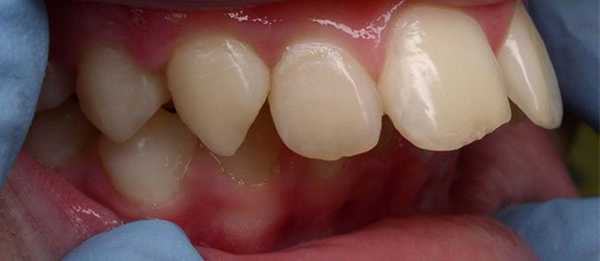

В полости рта дистальный прикус определяется по выступающим вперед верхним фронтальным зубам. В норме, при ортогнатическом прикусе, верхние резцы перекрывают нижние примерно на 1/3. При дистальной патологии между верхними и нижними резцами образуется расстояние — «саггитальная щель».

Определяющими внутриротовыми признаками дистального прикуса служат выдвижение вперед верхних фронтальных зубов; несмыкание верхних и нижних резцов с наличием между ними сагиттальной щели; нарушение взаимного расположения боковых зубов в переднезаднем направлении. В чистом виде дистальный прикус встречается редко; гораздо чаще он сочетается с аномалиями положения зубов, диастемой, тремами, глубоким, открытым или перекрестным прикусом, готическим нёбом.

У определенной группы пациентов с дистальным прикусом между нижними и верхними зубами присутствует продольная щель.

Если щели нет, это говорит о смещении верхних зубов в сторону гортани (в сторону рта). Если у кого-то такое смещение хорошо видно человеческим взглядом, то у небольшой категории пациентов при дистальном прикусе смещение верхних зубов можно определить только в стоматологическом кабинете.